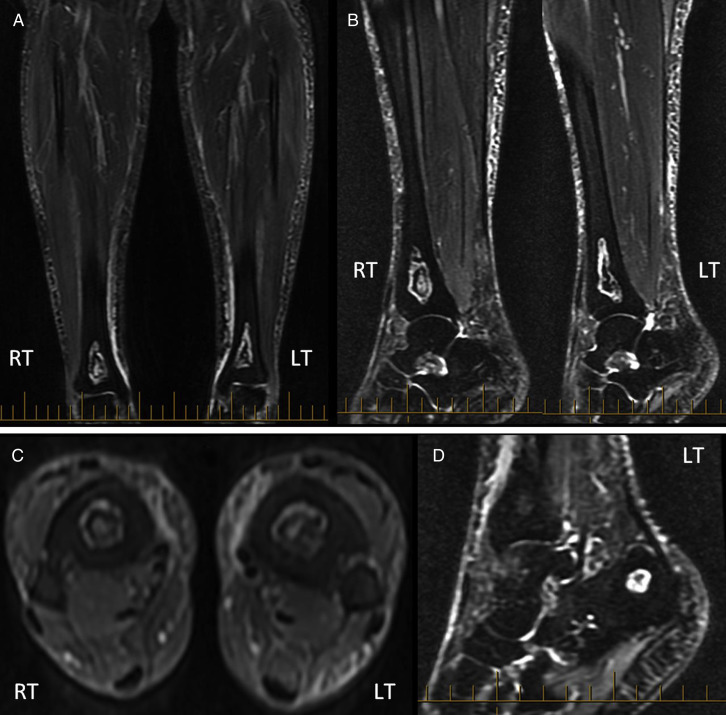

The previous surgeon she had consulted had ordered a magnetic resonance imaging study and diagnosed AVN of the bilateral distal tibias (Fig. 1 ). Subsequent magnetic resonance imaging studies showed ON in the left calcaneus and right humerus. Only her right tibia was symptomatic. For preoperative planning and to rule out any pathologic fractures, a computed tomography scan was ordered (Fig. 2 ).

Fig. 1.

Magnetic resonance imaging study showing relatively symmetrical lesions of avascular necrosis in the coronal (A), sagittal (B), and transverse (C) slices of the bilateral diaphyseal–metaphyseal junctions of the tibias. (D) Note the osteonecrotic lesion in the tubercle of the left calcaneus. LT, left; RT, right.